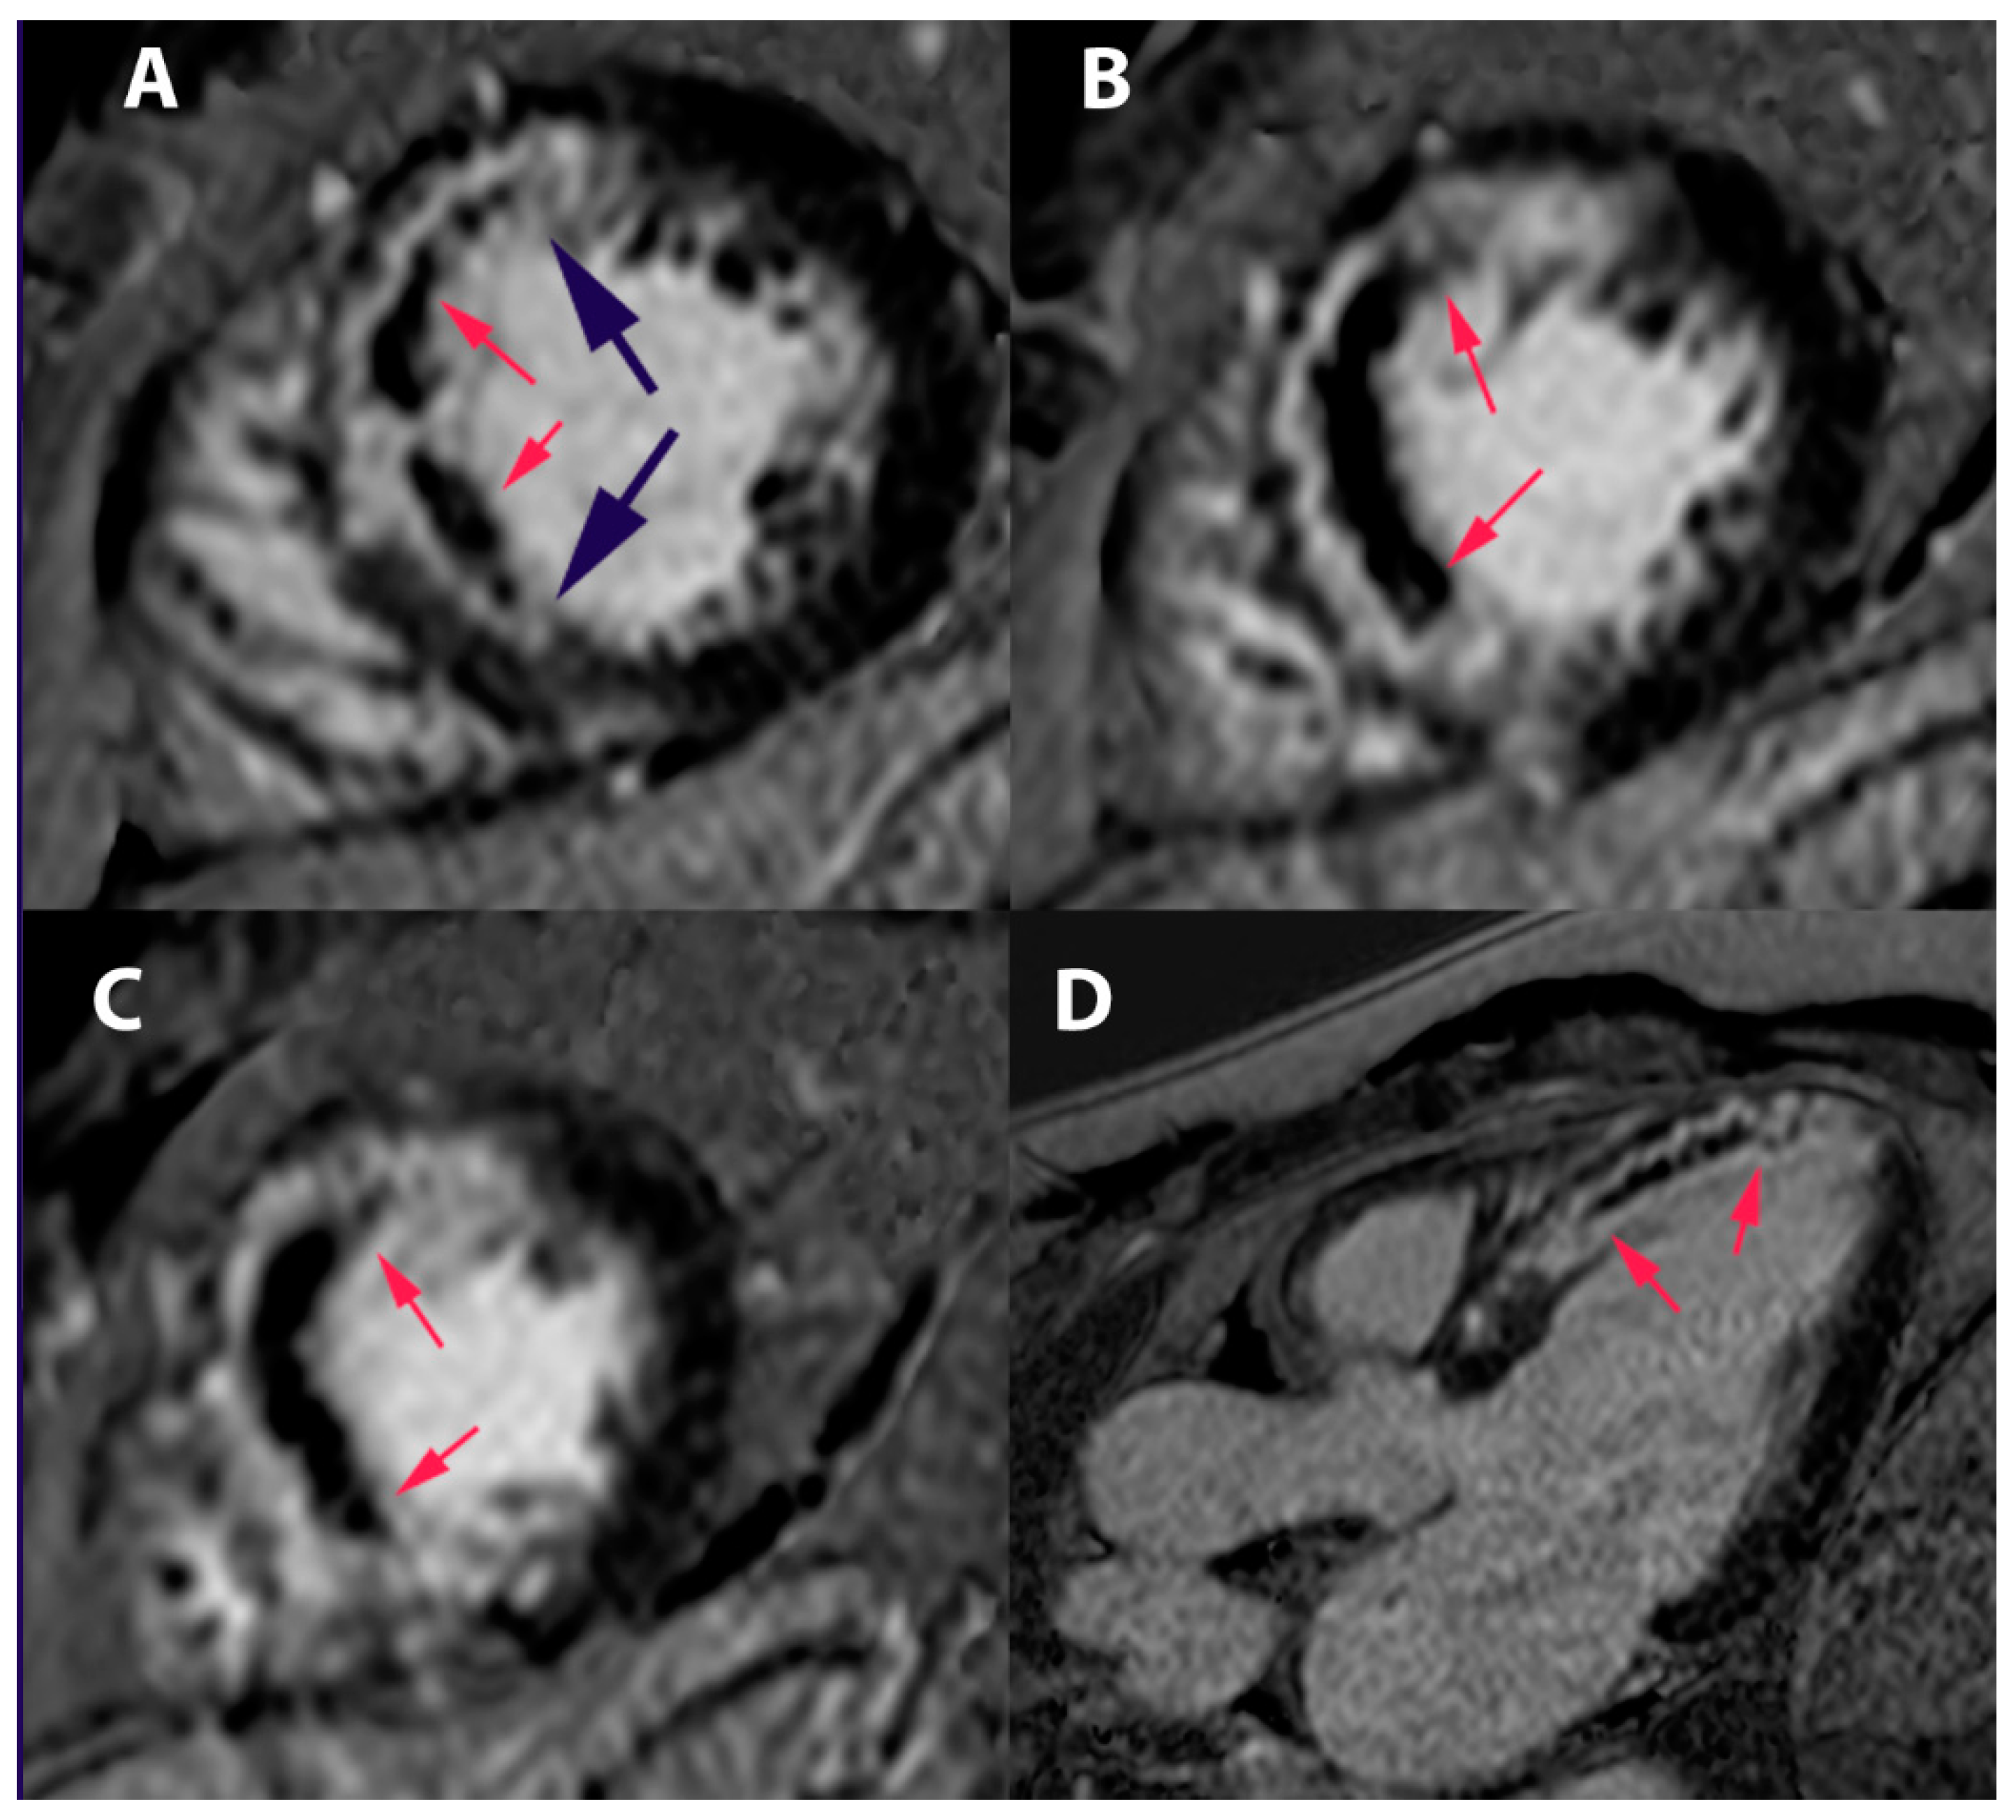

- Ferreira, V.M.; Schulz-Menger, J.; Holmvang, G.; Kramer, C.M.; Carbone, I.; Sechtem, U.; Kindermann, I.; Gutberlet, M.; Cooper, L.T.; Liu, P.; et al. Cardiovascular Magnetic Resonance in Nonischemic Myocardial Inflammation. J. Am. Coll. Cardiol. 2018, 72, 3158–3176. [Google Scholar] [CrossRef] [PubMed]

- Friedrich, M.G.; Sechtem, U.; Schulz-Menger, J.; Holmvang, G.; Alakija, P.; Cooper, L.T.; White, J.A.; Abdel-Aty, H.; Gutberlet, M.; Prasad, S.; et al. Cardiovascular magnetic resonance in myocarditis: A JACC White Paper. J. Am. Coll. Cardiol. 2009, 53, 1475–1497. [Google Scholar] [CrossRef] [PubMed]

| Cardiac Magnetic Resonance | Subendocardial or transmural late gadolinium enhancement (LGE) | LGE absent | Patch and epicardial LGE are common than subendocardial or transmural |

In the setting of clinically suspected myocarditis, CMR findings are consistent with myocardial inflammation, if at least two of the following criteria are present:

|

| A CMR study is consistent with myocyte injury and/or scar caused by myocardial inflammation if criterion 3 is present |